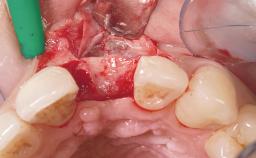

A 42-year-old female patient was referred to our clinic at the School of Dentistry of the University of São Paulo in November 2004, presenting a deficient restoration in the upper left central incisor. The clinical examination revealed no gingival retraction or any signs of gingival inflammation and, therefore, previous periodontal treatment was not considered. The patient presented a high lip line at full smile and a thin tissue biotype. This combination characterized a high-risk situation from an anatomic point of view, which required careful preoperative planning and cautious surgical execution.

Placement Protocol Immediate implant placement

Tooth Site Maxillary incisor or canine

Socket Integrity Sufficient, with intact bone walls

Bone Volume Sufficient, with intact walls

Loading Protocol Immediate